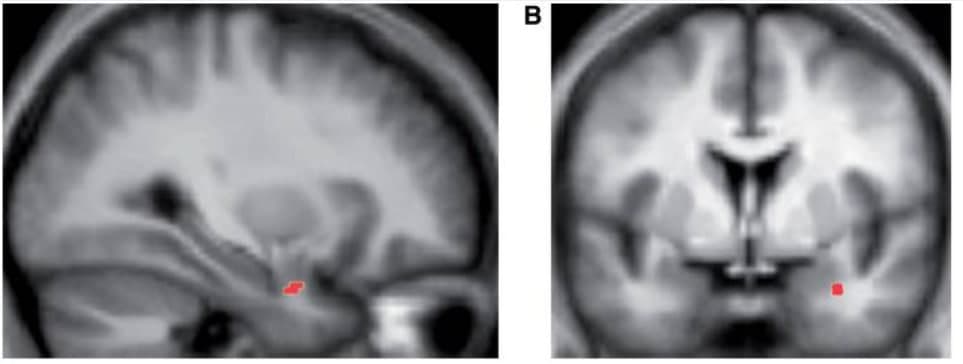

Лазар привлекла 16 человек, которые никогда не медитировали. Поместила их в томограф и сделала контрольный снимок мозга. Затем каждому предложила программу ежедневной медитации осознанности: всего 30-40 минут в день на протяжении восьми недель. По прошествии этого периода всех испытуемых снова обследовали в томографе. Что же увидела Лазар и ее коллеги? Во-первых, увеличенный гиппокамп — область мозга, ответственная за память, обучение и регуляцию эмоций. Во-вторых, уменьшенную миндалину, которую часто связывают с реакцией «бей или беги». Обычно она активируется при стрессе. Интересно, что ее сокращение коррелировало с оценкой самих испытуемых. Те отмечали сниженный уровень стресса после двухмесячного курса.

На снимке указана зона миндалины, которая уменьшилась после эксперимента